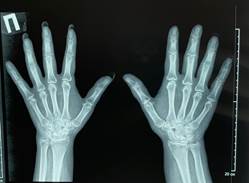

При осмотре обращала на себя внимание дефигурация левого коленного сустава, ПМФС кистей, правого голеностопного сустава за счет экссудативных проявлений, множественные тофусы периартикулярных тканей (Рис.1). Болевой синдром по ВАШ 65-70 мм.

Рисунок 1. Изменения верхних (а,в) и нижних (в) конечностей пациентки (описание в тексте)

При лабораторном исследовании крови макроцитарная гиперхромная анемия с уровнем гемоглобина 83 г\л, лейкопения - 3.18 х 10 ⁹/л, повышение СОЭ - 24 мм\ч, СРБ - 12.83 мг\л. Концентрация в крови мочевины 2.58 ммоль\л, креатинина - 72.5 мкмоль\л, гамма-глутамилтрансферазы - 167.8 Ед\л, , мочевой кислоты - 625.8 мкмоль\л, щелочной фосфатазы - 140 Ед\л. Скорость клубочковой фильтрации - 92 мл\мин\1.73 м². Уровень ферритина был 111.31 нг\мл, витамина В12 - 141 пг\мл. Остальные биохимические показатели крови и общий анализ мочи без особенностей. Электрокардиографически – синусовый ритм с ЧСС 67 в минуту, изменения миокарда. Заключение ЭХО-КГ: полости сердца не расширены, уплотнены створки аортального и митрального клапана, легочная гипертензия 0-1 степени (31+5 мм.рт.ст.), глобальная сократимость левого желудочка хорошая. Ультразвуковое исследование органов брюшной полости и почек не выявило патологии. Рентгенография органов грудной полости без патологии. По данным рентгенографии коленных суставов выявлен двусторонний гонартроз II стадии, кистей – рентгенологические признаки артрита II стадии (Рис.2). На рентгенограмме стоп определялся выраженный остеопороз, суставные щели обоих плюсне-фаланговых сочленений равномерно сужены, уплотнены суставные поверхности, в проекции головок плюсневых костей – пробойники, что характерно для подагрического артрита слева II стадии, справа III-IV стадии (Рис.3). По данным авторов, умеренные рентгенологические изменения суставов возникают в среднем через 9 лет, а более значительные через 10-15 лет и более [5]. У наблюдаемой нами пациентки рентгенологические изменения были выявлены уже через 5 лет от начала заболевания.

Рисунок 2. Рентгенограммы коленных суставов (а) и кистей (б) пациентки М. (пояснение в тексте)